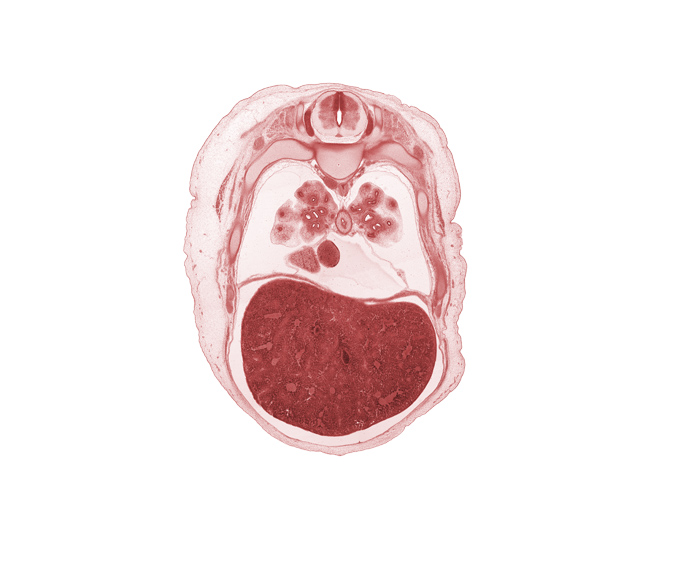

Carnegie Embryo #462 | Location: 6-01-01

Keywords: T-5 spinal ganglion, anterior basal segmental bronchus, aorta, azygos vein, diaphragm, dorsal horn of grey matter, edge of right atrium, external intercostal muscle(s), head of rib 6, inferior vena cava, lateral horn of grey matter, left lobe of liver, liver prominence, medial basal segmental bronchus, neural arch, oblique fissure, pericardial cavity, peritoneal cavity, rib 7, right lobe of liver, trapezius muscle, ventral horn of grey matter

Source: The Virtual Human Embryo.